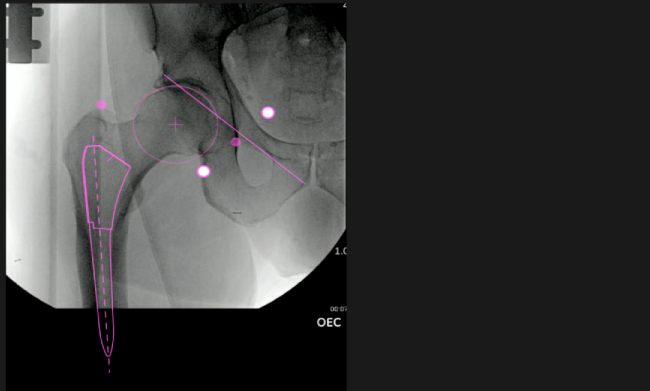

Mayor nivel de información intraoperatoria facilita la colocación correcta de los implantes:

Inclinación y anteversión de la copa acetabular para una correcta colocación del implante.

Desplazamiento y offset para posicionamiento óptimo del componente (vástago) femoral.

Verificación de la posición deseada del implante que potencialmente puede ayudar a reducir la probabilidad de dislocación protésica y aumentar la estabilidad de la articulación.